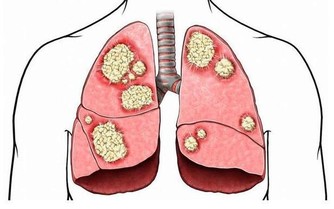

高血壓,是指以體循環動脈血壓(收縮壓和/或舒張壓)增高為主要特徵(收縮壓≥140毫米汞柱,舒張壓≥90毫米汞柱),可伴有心、腦、腎等器官的功能或器質性損害的臨床綜合徵。高血壓是最常見的慢性病,也是心腦血管病最主要的危險因素。